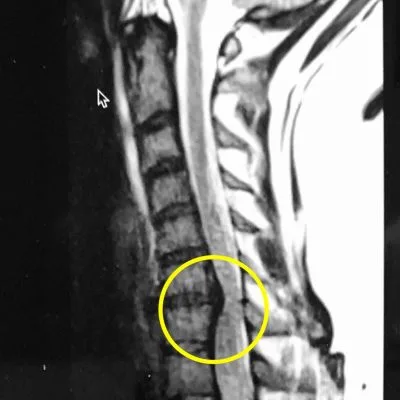

그러고 그날 저녁 mri를 찍고 결과를 기다렸다. 의사가 네 시간 후 오더니 디스크라고 이야기해 줬다. Bulging round form이라고 하니 bulging disc인 게 확실해졌다.

내것은 아니지만 튀어나온 디스크의 예시.